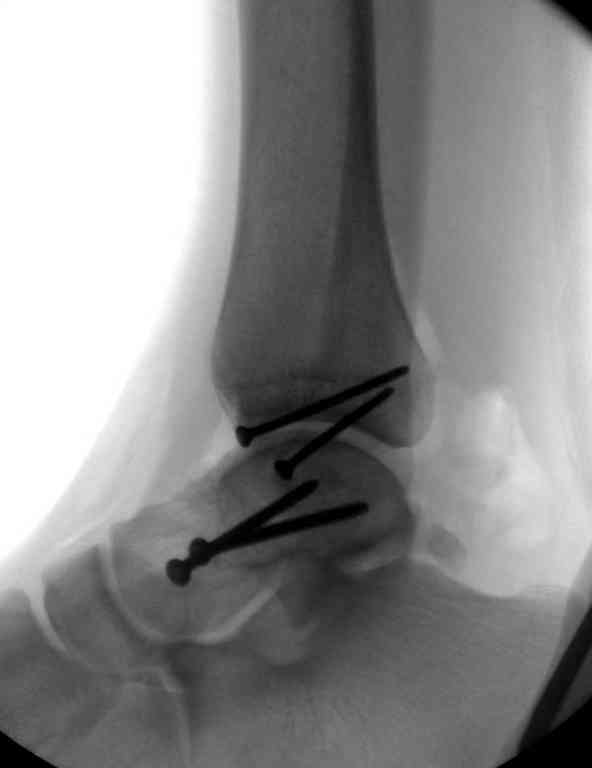

Вчера провели фиксацию.

Из-за многооскольчатости дистальной части малоберцовой, где невозможно было провести фиксацию шурупами, перелом зафиксирован подпирающей пластиной, которая должна служить дополнением отсутствующей дистальной части малоберцовой (lateral cortex substitute).

Для стабильности два шурупа на синдесмоз.

Медиальную рану с приближенными краями продолжаем вакуумировать (KCI). Наружный фиксатор оставлен на пару недель, надеюсь, небольшая рана будет гранулировать и закроется без кожной пластики. Фиксация медиальной ложыжки не планируется.

Прооперировали таранную кость, доступ внутренний без пересечения внутренней лодыжки. Хотя покаялись, что не пошли на остеотомию лодыжки внутренней. Винт

провели через небольшой передний доступ.